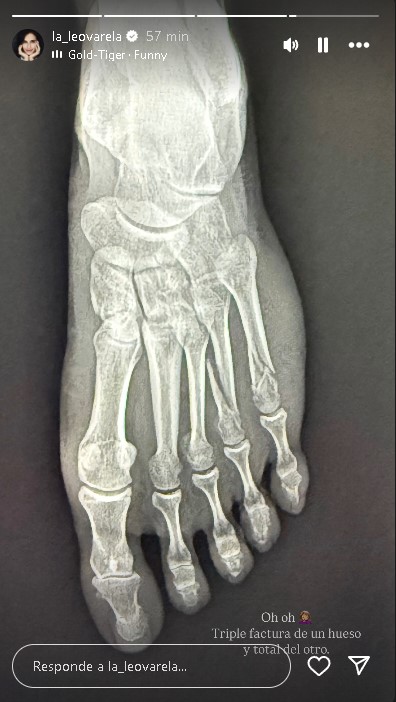

Más adelante subió otra fotografía donde aparecía una radiografía a su pie izquierdo con un diagnóstico más preocupante. "Oh, oh. Triple fractura de un hueso y total del otro", escribió la actriz, lamentando el accidente que sufrió y que, seguramente, le generará inconvenientes en sus proyectos personales y laborales.